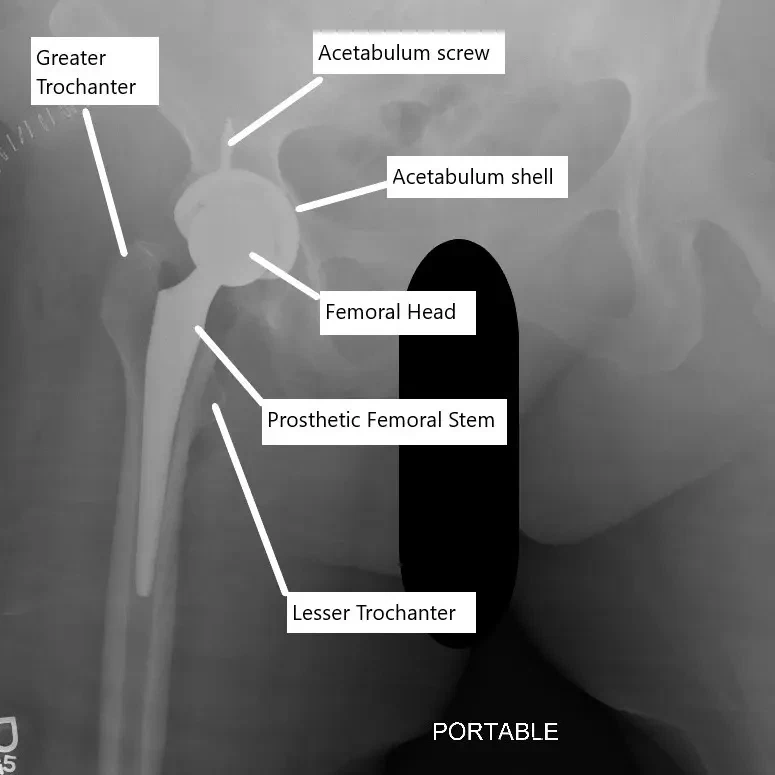

X-ray showing total hip replacement

The acetabulum socket is freshened with help of a reamer. The freshening of the bone in the socket helps the bone to grow on and in the acetabulum implant (cup). The reaming of the acetabulum socket is done in a position that allows maximum movement of the joint while maintaining stability. The prosthetic cup is press-fitted and may be additionally fixed to the acetabulum using screws.

Upon satisfaction with the size of the trial implants, the surgeon inserts the prosthetic femoral stem in the prepared upper thigh bone. The stem is press-fitted in the canal with a special emphasis on the direction and the angle of the final position. The stem is mostly press-fitted but may be fixed with bone cement in limited cases.

A prosthetic head made of metal alloy or ceramic is placed upon the neck. The metallic acetabulum socket is covered with a high-grade plastic liner. The head is placed back in the socket. The capsule as well as the cut short external rotators are repaired. The incision is closed in layers and a bandage is placed on the skin incision.